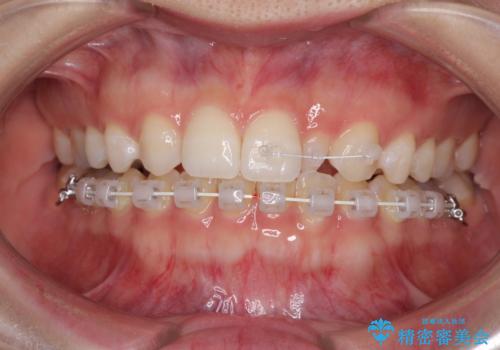

海外転居前に気になる前歯を整えたい 上下前歯の部分矯正

- 1年後に海外に転居するため、気になる前歯を矯正治療で整えたいとのことで来院された患者様です。

下顎は叢生が強かったため、奥歯までワイヤーを装着し、上顎は前歯の一部のみ気になっていたので、その部分にだけワイヤー装置を装着することとしました。